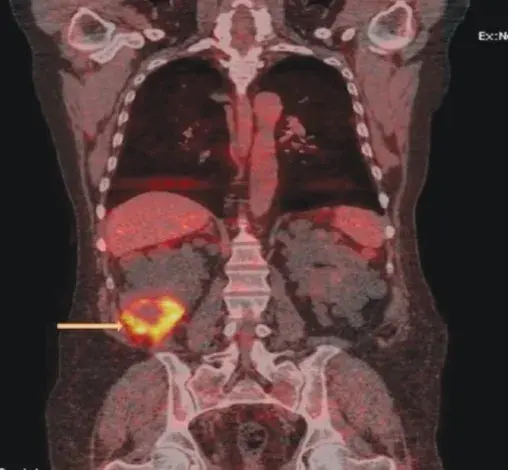

Manejando un caso de infección cística en un paciente con DRPAD

Manejando un caso de infección cística en un paciente con DRPAD

Manejando un caso de infección cística en un paciente con DRPAD

Manejando un caso de infección cística en un paciente con DRPADValkercyo Feitosa